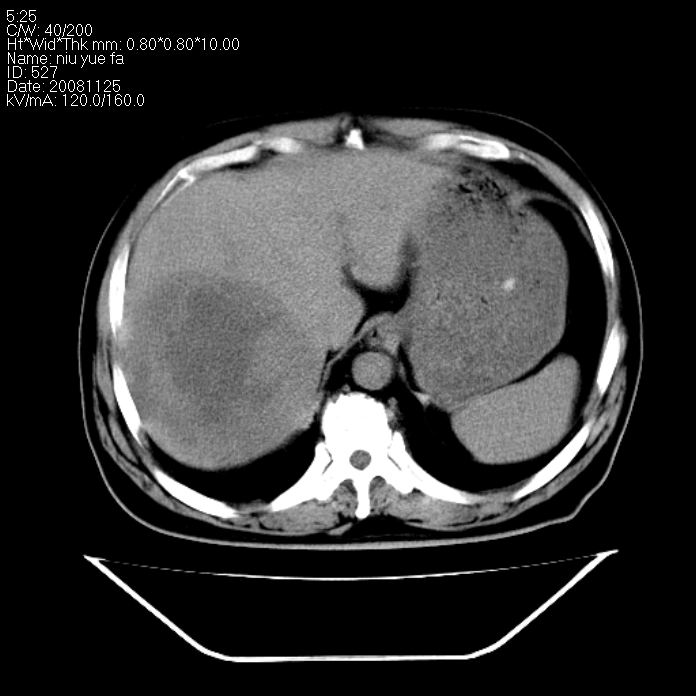

巨块型肝癌,坏死,出血;胆囊结石

1)考虑肝右叶巨块型肝癌并坏死、出血;建议行ct增强扫描检查进一步明确诊断。2)胆囊结石,胆囊炎。

考虑肝右叶巨块型肝癌并坏死、出血;建议行ct增强扫描。胆囊结石。

支持: 1)考虑肝右叶巨块型肝癌并坏死、出血;建议行ct增强扫描检查进一步明确诊断。2)胆囊结石,胆囊炎。

肝右叶巨块型肝癌并坏死、出血;胆囊结石,胆囊炎。